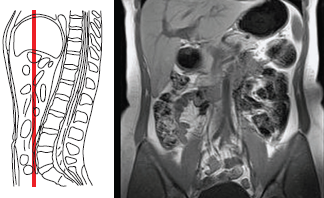

Магнитно-резонансная томография (МРТ) органов брюшной полости может и должна проводиться на высокопольных томографах с напряженностью магнитного поля от 1,5 Тесла. В отделении лучевой диагностики нашим пациентам предлагается пройти МРТ органов брюшной полости на томографе с магнитным полем силой 3,0 Т (тесла). Ограничение по весу (для пациента с большим весом) при проведении магнитно-резонансной томографии (МРТ) брюшной полости 3,0 Т (тесла) — не более 200 кг.

Магнитно-резонансная томография (МРТ) органов брюшной полости — печени, желчного пузыря, системы и поджелудочной железы — желательно проводить после предварительного ультразвукового обследования этого анатомического региона. Желательно принести с собой заключения и изображения, полученные при исследовании, даже если при УЗИ не было найдено патологии.

Магнитно-резонансная томография (МРТ) органов брюшной полости (печени и поджелудочной железы) 3,0 Т (тесла) показана:

- при подозрении на первичное или вторичное опухолевое поражение печени и желчных протоков, жировую дистрофию, абсцессы, объемные образования (кисты, в том числе паразитарные), цирроз печени;

- при наличии клинической картины механической желтухи;

- для оценки в динамике эффективности лечения опухолевого поражения;

- при гепатомегалии неизвестной природы;

- при травматических повреждениях;

- при гепато-церебральной дистрофии;

- при холелитиазе для исключения или подозрении на наличии конкрементов в желчных протоках

- при острых и хронических панкреатитах;

- при подозрении на объемное образование, первичное и вторичное опухолевое поражение;

- при ишемических поражениях паренхиматозных органов брюшной полости.